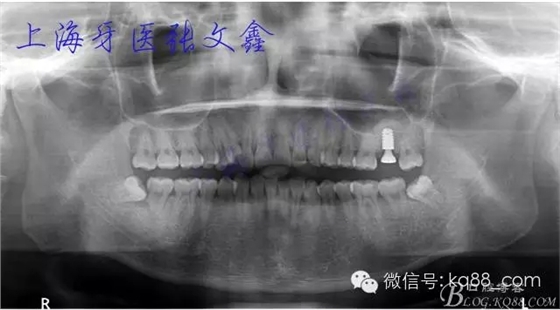

術(shù)后全景片